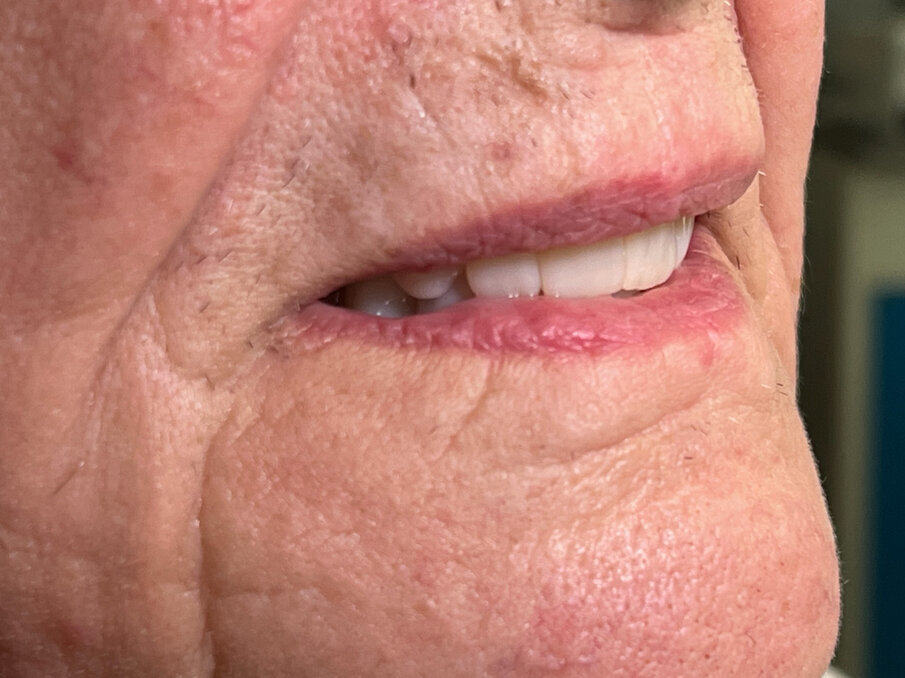

Paziente femmina di 75 anni in buona salute psico-fisica. Presenta una riabilitazione su impianti nell’arcata superiore con diffusa perimplantite e sindrome della bocca urente. Nell’arcata inferiore presenta protesi totale completa con denti abrasi e incongruenza tra le basi e i processi alveolari (Figg. 1-13).

Fig. 1_Volto in prima visita.

Fig. 2_Fotografia intraorale: la paziente riferisce dolore e sanguinamento all’arcata superiore con stabilità compromessa della protesi inferiore.